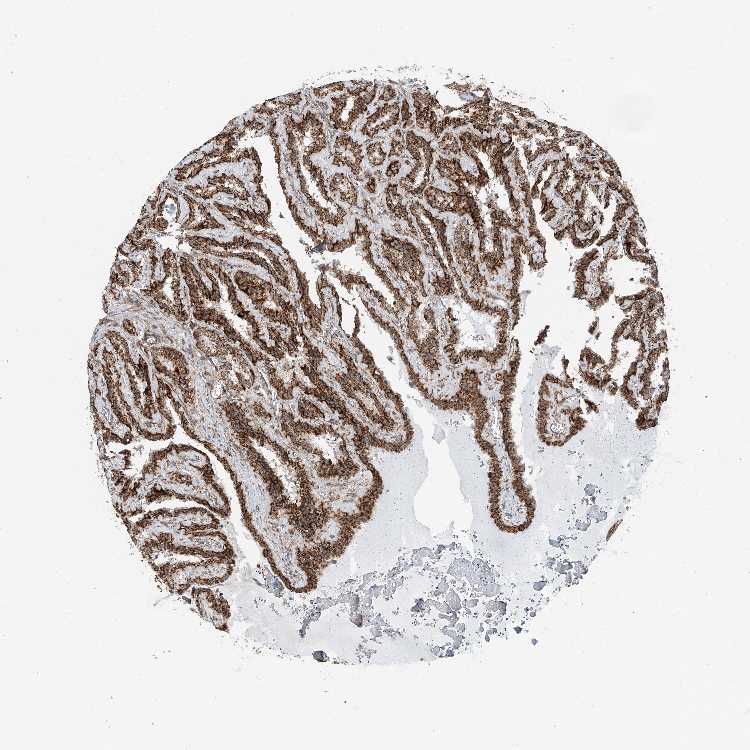

ABCC11